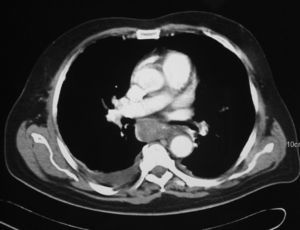

Varón de 68 años de edad, con antecedentes de hipertensión arterial bien controlada con tratamiento médico, que consultó en el servicio de urgencias por dolor centrotorácico opresivo acompañado de disnea. En el electrocardiograma se apreció una fibrilación auricular; las enzimas de isquemia miocárdica y la radiografía de tórax resultaron normales. En la analítica se detectó un dímero D de 880ng/ml (normal hasta 500) que, acompañado del cuadro clínico, hizo pensar en una tromboembolia pulmonar (TEP). Ante esta sospecha se anticoaguló al paciente con un bolo intravenoso de 50mg de heparina sódica más 80mg de enoxaparina por vía subcutánea, en espera de una gammagrafía pulmonar que confirmara el diagnóstico. El paciente empeoró y aumentó el dolor torácico, razón por la que se le realizó una tomografía computarizada (TC) torácica y abdominal, la que descartó la presencia de un aneurisma disecante de aorta pero mostró un engrosamiento del esofágico torácico con áreas de distinta densidad compatible con un hematoma intramural (fig. 1).